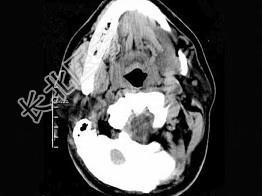

- 单项选择题男,32岁, 左侧下颌部肿块,CT如图所示, 最可能的诊断是 ( )

A、造釉细胞瘤

B、颌骨囊肿

C、鳃裂囊肿

D、颈部淋巴管瘤

E、舌下腺囊肿